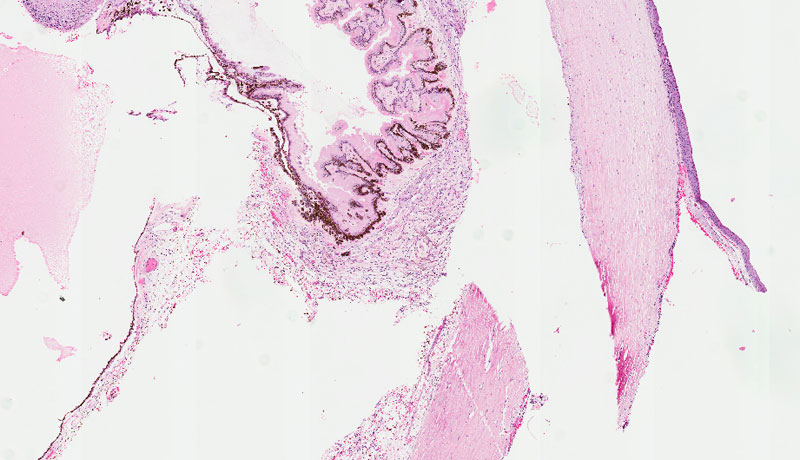

DISEASE: Pseudoexfoliation

PATHOGENESIS: Progressive accumulation of fibrillar material in tissues throughout the anterior segment that may be a stress-induced elastosis. Associated with mutations in lysyl oxidase-like 1 gene, LOXL1 on 15q24.

HISTOLOGY FEATURES: Abnormal, iron filings, appear on the anterior lens capsule. Pigmentation and small clumps of eosinophilic material in the anterior chamber. Iris pigment has a saw tooth configuration.

OCULAR FEATURES: Also known as an exfoliation syndrome. Typically occur in patients older than 50. Cause of secondary glaucoma with material in the trabecular meshwork.